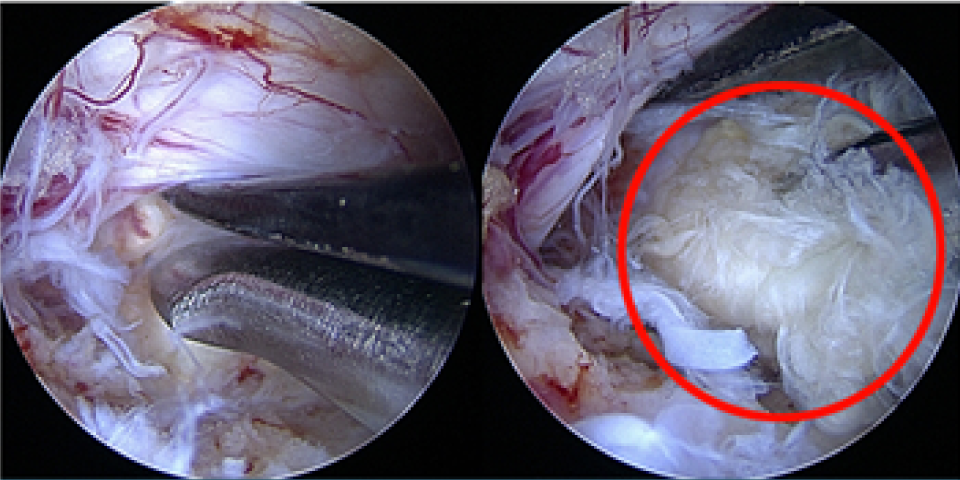

터진 디스크를 내시경으로 제거하는 모습